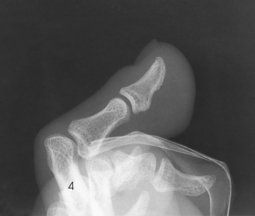

The foot consists of 26 bones (Figs. 6-1 and 6-2):

The bones of the foot are similar to the bones of the hand. Structural differences permit walking and support of the body’s weight. For descriptive purposes, the foot is sometimes divided into the forefoot, midfoot, and hindfoot. The forefoot includes the metatarsals and toes. The midfoot includes five tarsals—the cuneiforms, navicular, and cuboid bones. The hindfoot includes the talus and calcaneus. The bones of the foot are shaped and joined together to form a series of longitudinal and transverse arches. The longitudinal arch functions as a shock absorber to distribute the weight of the body in all directions, which permits smooth walking (see Fig. 6-2). The transverse arch runs from side to side and assists in supporting the longitudinal arch. The superior surface of the foot is termed the dorsum or dorsal surface, and the inferior, or posterior, aspect of the foot is termed the plantar surface.

Each foot has 14 phalanges—2 in the great toe and 3 in each of the other toes. The phalanges of the great toe are termed the distal and proximal phalanges. The phalanges of the other toes are termed the proximal, middle, and distal phalanges. Each phalanx is composed of a body and two expanded articular ends—the proximal base and the distal head.

The five metatarsals are numbered one to five beginning at the medial or great toe side of the foot. The metatarsals consist of a body and two articular ends. The expanded proximal end is called the base, and the small, rounded distal end is termed the head. The five heads form the “ball” of the foot. The first metatarsal is the shortest and thickest. The second metatarsal is the longest. The base of the fifth metatarsal contains a prominent tuberosity, which is a common site of fractures.

The proximal foot contains seven tarsals (see Fig. 6-1):

Beginning at the medial side of the foot, the cuneiforms are described as medial, intermediate, and lateral.

The cuboid bone lies on the lateral side of the foot between the calcaneus and the fourth and fifth metatarsals (see Fig. 6-1). The navicular bone lies on the medial side of the foot between the talus and the three cuneiforms. The cuneiforms lie at the central and medial aspect of the foot between the navicular bone and the first, second, and third metatarsals. The medial cuneiform is the largest of the three cuneiform bones, and the intermediate cuneiform is the smallest.

Beneath the head of the first metatarsal are two small bones called sesamoid bones. They are detached from the foot and embedded within two tendons. These bones are seen on most adult foot radiographs. They are a common site of fractures and must be shown radiographically (see Fig. 6-2).